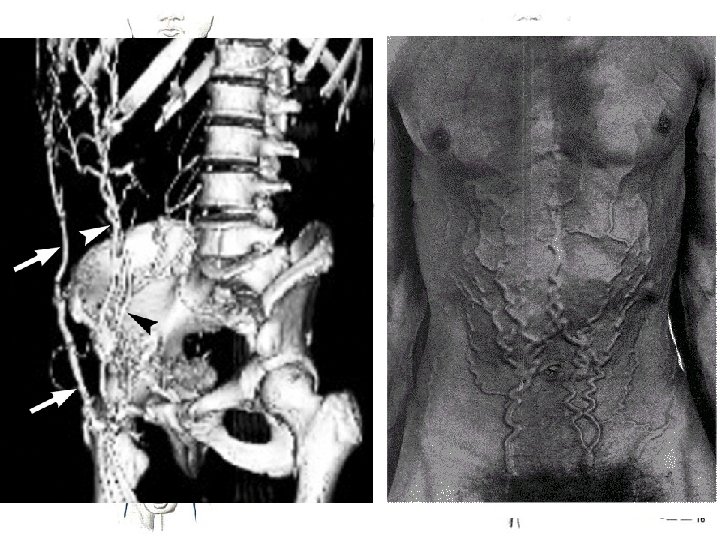

Vein of LL – 3 D-flebo. CT VSP varices Dodd

Veins of lower limb • superficial system – compartimentum saphenum • deep system - accompany arteries - doubled up to fossa poplitea - frequent connections around artery - frequent valves • systema venosum laterale (Albanesei)

Deep veins of lower limb • • • vena femoralis communis venae comitantes arteriarum perforantium plexus venosus genicularis venae soleales + venae gastrocnemii vena ischiadica – rare – often connected with Klippel-Trenaunay-Weber‘s syndrome • veins with varices, skin hemangioms, hypertrophy of soft tissues and bones)

Varices • change of blood flow direction venous hypertension ischaemia

Veins of LL – clinical relevance • • chronic venous insufficiency superficial thrombophlebitis deep venous thrombosis – thrombembolic disease varices – primary (collagen disorder), secondary – treatment: phlebectomy (stripping) + crossectomy, miniinvasive operation (CHIVA – La Cure Hémodynamique de l'Insuffisance Veineuse en Ambulatoire), endovenous laser (EVLT), sclerotization, radiofrequency endoluminal ablation • venous leg ulcer • lung embolia